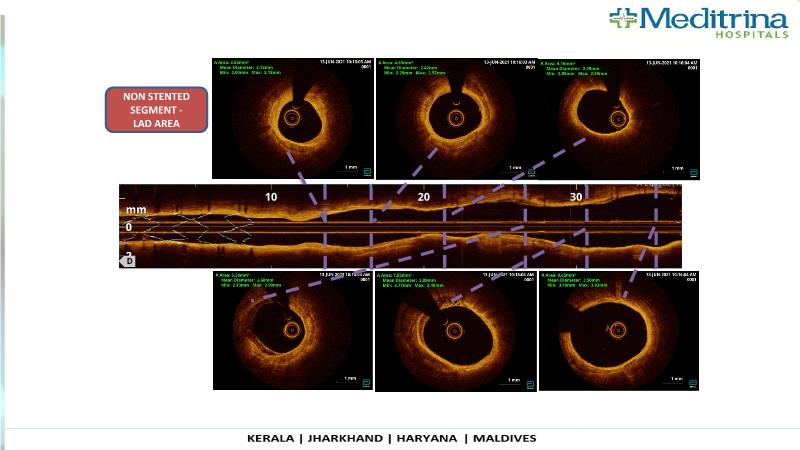

- To define the use of OCT in PCI of complex coronary lesions